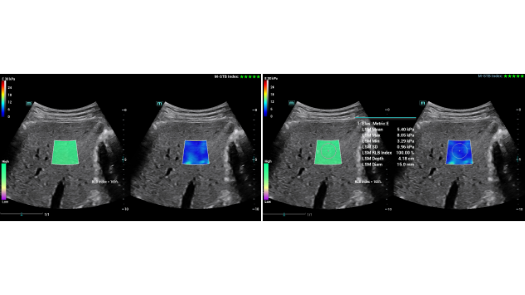

Stworzona specjalnie dla U?ytkownikÃģw z zakresu podstawowej opieki zdrowotnej, Consona wykorzystuje nowe rozwi?zania, ktÃģre efektywnie pomog? wykona? bez problemu diagnostyk? u rÃģ?nych pacjentÃģw.

Bez wzgl?du na to, czy pracujesz w szpitalu, przychodni, czy u?ywasz ultrasonografu do badaÅ ogÃģlnych, w opiece zdrowotnej kobiet lub w badaniach sercowo-naczyniowych, w serii Consona znajdziesz bardzo pot??ne narz?dzia, aby utrzyma? si? w czo?Ãģwce.